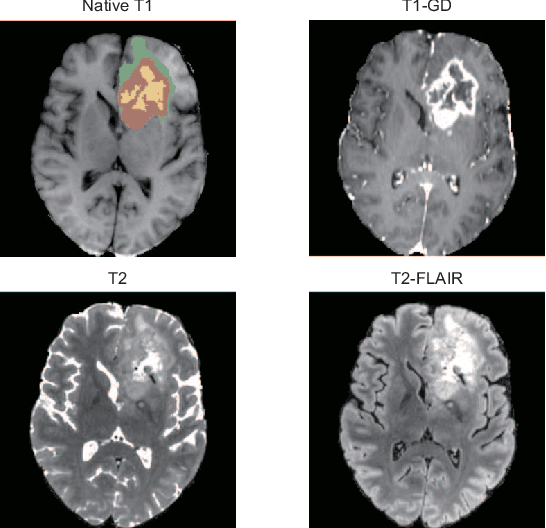

Abstract:Brain tumor segmentation is essential for the diagnosis and prognosis of patients with gliomas. The brain tumor segmentation challenge has continued to provide a great source of data to develop automatic algorithms to perform the task. This paper describes our contribution to the 2021 competition. We developed our methods based on nn-UNet, the winning entry of last year competition. We experimented with several modifications, including using a larger network, replacing batch normalization with group normalization, and utilizing axial attention in the decoder. Internal 5-fold cross validation as well as online evaluation from the organizers showed the effectiveness of our approach, with minor improvement in quantitative metrics when compared to the baseline. The proposed models won first place in the final ranking on unseen test data. The codes, pretrained weights, and docker image for the winning submission are publicly available at https://github.com/rixez/Brats21_KAIST_MRI_Lab